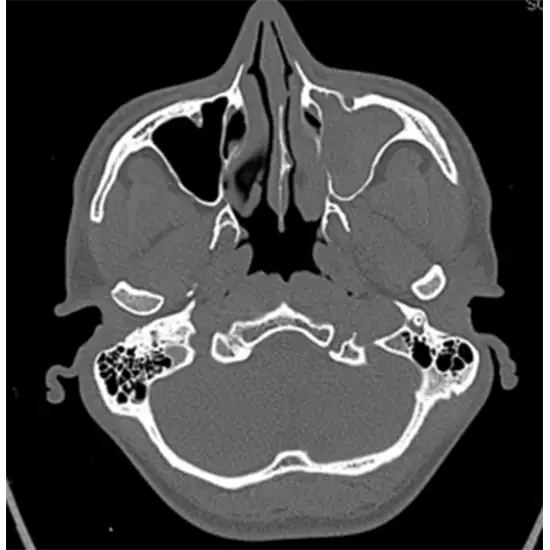

CT (Computed Tomography) Head and PNS (Para Nasal Sinus ) is an imaging procedure that creates clear images of the head and PNS( Coronal Section). This is used to diagnose the disorders of the brain such as brain tumors, stroke, etc. as well as detect fluid accumulation in the sinus, fracture, trauma, or increase in tissue thickness. It is helpful in assessing the enhanced lesions. This view involves frontal and ethmoid sinuses with the erosion of the floor and orbital extension.